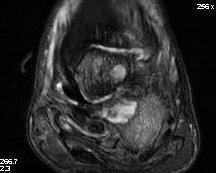

- MRI

Forefoot - diabetic foot ulcer with evidence of underlying osteomyelitis

Hindfoot - calcaneal osteotomyelitis

Charcot arthropathy

Midfoot ulcer with evidence of underlying Charcot arthropathy and midfoot collapse